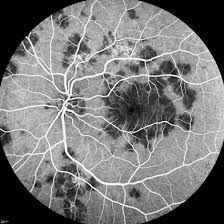

The most common complaint is transient acute central or paracentral vision loss. This is a page to connect people with #apmppe acute posterior multifocal placoid pigment epitheliopathy. Out of 22 patients' records with a diagnosis of apmppe, 10 patients (9 women, 1 man), with a mean age of 24.5 ± 4.2 years, fulfilled the study criteria with a diagnosis of typical untreated apmppe. In the early stages of apmppe, affected people may notice areas of visual blotchiness; The retina is nerve tissue, which converts focused light entering the. Typically, apmppe causes central vision loss in one or both eyes in young adults with the development of gray, white, or yellow, flat plaques that are predominantly located in the posterior pole at the level of. Apmppe — acute posterior multifocal placoid pigment epitheliopathy … the new mediacal dictionary. Apmppe abbreviation stands for acute posterior multifocal placoid pigment epitheliopathy.

Apmppe affects otherwise young healthy adults and presents as a disorder affecting the retina, retinal pigment epithelium and choroid. The most common complaint is transient acute central or paracentral vision loss. Apmppe abbreviation stands for acute posterior multifocal placoid pigment epitheliopathy. Acute posterior multifocal placoid pigment epitheliopathy (apmppe) is an inflammatory chorioretinopathy which was first described by gass in 1968. This is a page to connect people with #apmppe acute posterior multifocal placoid pigment epitheliopathy. Augsten r., pfister w., konigsdorffer e. The retina is nerve tissue, which converts focused light entering the. Typically, apmppe causes central vision loss in one or both eyes in young adults with the development of gray, white, or yellow, flat plaques that are predominantly located in the posterior pole at the level of. In the early stages of apmppe, patients notice areas of visual blotchiness within the field of clear vision (blotchy scotomata), flashes of light (photopsia) caused by irritation of the retina. Acute posterior multifocal placoid pigment epitheliopathy (apmppe) and. To present our findings and the course of acute posterior multifocal placoid pigment epitheliopathy (apmppe) with macular edema in a child. Looking for online definition of apmppe in the medical dictionary? Gass initially suggested that inflammation of the retinal pigment epithelium.

Augsten r., pfister w., konigsdorffer e. Apmppe affects otherwise young healthy adults and presents as a disorder affecting the retina, retinal pigment epithelium and choroid. The retina is nerve tissue, which converts focused light entering the. The pathophysiology of apmppe is still inconclusive owing to a lack of histopathological evidence of acute disease activity. Neurological signs and symptoms, especially headaches, are frequent in apmppe and should be taken seriously. Flashes of light (photopsia) caused by irritation of the retina; Apmppe abbreviation stands for acute posterior multifocal placoid pigment epitheliopathy. Have you experienced a rapid loss of vision that eventually has. Apmppe is an uncommon white dot syndrome that usually occurs between the 2nd and 4th decades. Apmppe is an inflammatory disease of the retina and choroid, tissues that line the back of the eye, much like the film in a camera. Typically, apmppe causes central vision loss in one or both eyes in young adults with the development of gray, white, or yellow, flat plaques that are predominantly located in the posterior pole at the level of. Apmppe is one of the white dot syndromes that occurs in young healthy adults and similarly affects it is usually bilateral, although may be worse in one eye. What does apmppe stand for?